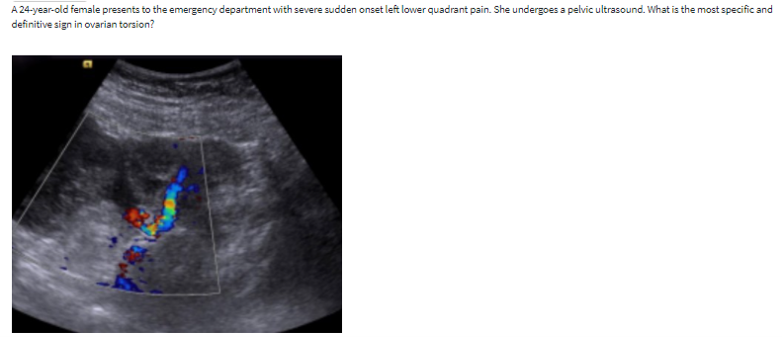

twisted vascular pedicle

image shows a twisted vascular pedicle extending into an enlarged and hypoechoic ovary. a twisted vascular pedicle is detected in about 88% of torsion cases. It is considered the most specific and definitive sign of torsion.

most sensitive and specifics signs for ovarian torsion

sensitive sign: enlarged ovary (typically > 25mL)

Specific sign: whirpool sign (twisting of the pedicle)

Additional findings include: